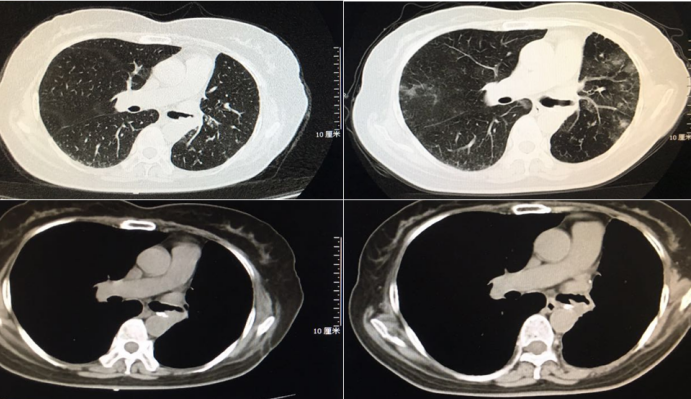

病例3(上海长海医院病例),中年男性,慢性起病。反复咳嗽、咳痰3年余,加重1个月。胸部CT提示右主支气管新生物。

图片

支气管镜检查发现右主支气管有菜花样宽基底赘生物。

胸部CT增强扫描右主支气管分布强化的血管影。